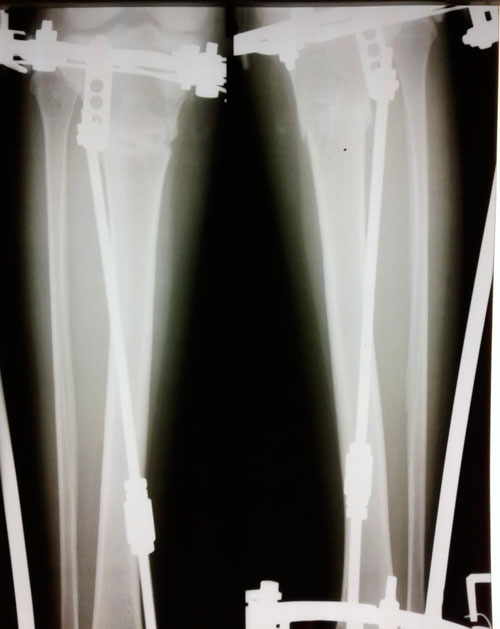

Рентген в 60 дней.

"Сращение идёт отлично! Ждем на снятие аппаратов, через 2 недели."